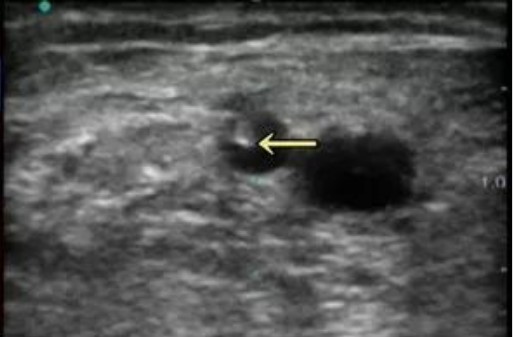

*测量距皮深度与血管内径

【超声】穿刺困难者推荐超声实时引导穿刺,能够减少穿刺失败次数。

2.2 新建内瘘的成熟与穿刺点确认,运用超声技术可以更方便的了解内瘘成熟情况与可穿刺段血管的情况!

>> 全面超声评估待穿刺血管段后决定穿刺点(如避开神经动脉);

将探头放置在血管进针点正上方,血管位于超声图像中间,根据距皮深度决定皮肤进针点和进针角度。

⑨针尖进入血管腔,看到白点在黑色的管腔内,此时不一定有回血